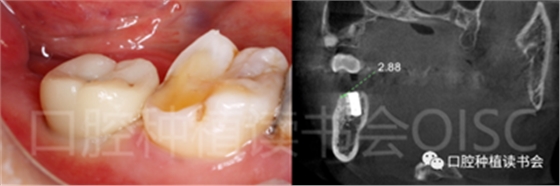

5.3.8 術(shù)后第3周,拔除48近中傾斜阻生智齒,觀察47位點(diǎn)愈合良好(圖21)。

圖21 拔除傾斜阻生的48,利于47后期的修復(fù)。

5.3.9 術(shù)后第6周,47行種植2期手術(shù),可見種植體周圍愈合良好,牙齦成型后,旋入愈合基臺(tái)(圖22)。

圖22 種植體周圍獲得了良好的骨整合。

5.4.4 種植冠封閉螺絲孔后,調(diào)合,拋光,完成最終修復(fù)(圖27);戴牙前CBCT顯示:種植體頰側(cè)骨板厚度為2.88mm;47種植冠獲得了良好的穿齦輪廓,并維持了正常的頰側(cè)牙弓輪廓。